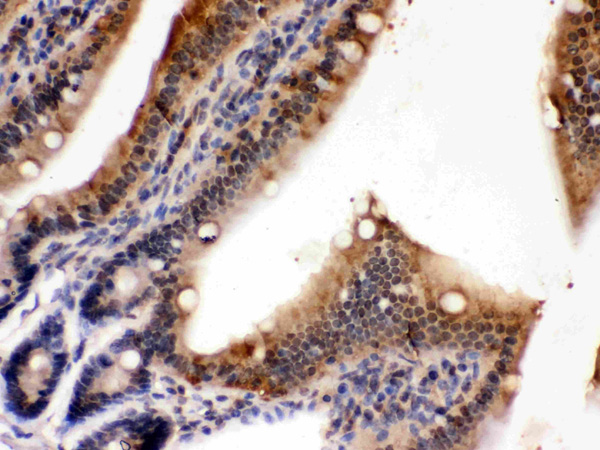

Cdc20/P55 Cdc, Polyclonal Antibody (Cat# AAA19132)